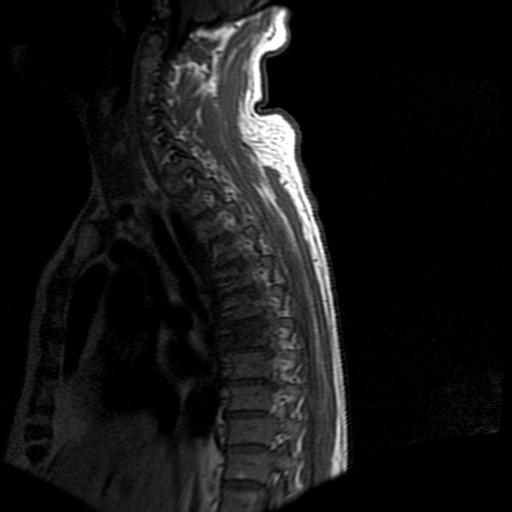

68岁男性,胸部疼痛,不适。

t7椎体前1/3信号略减低,椎体上下面凹陷,相应脊髓几周边软组织信号未见改变。考虑:椎体退变。

胸7椎体楔状变形及信号异常,附件未见明显异常信号.椎间隙正常.未见软组织块影.考虑骨质疏松所致压缩性骨折可能大.

胸7椎体楔状变形及信号异常[t1t2 均为低信号],附件未见明显异常信号.椎间隙正常.未见软组织块影.考虑陈旧性压缩性骨折伴退变。

首先需除外单发成骨性转移瘤可能。

转移瘤也不能排除